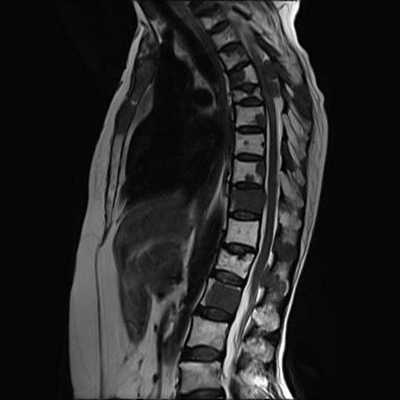

МРТ позвоночника дает более полное представление о строении мягких тканевых структур. Она эффективна, чтобы выявить наличие опухолей и воспалительных изменений в позвоночных суставах, межпозвоночных дисках, спинном мозге, нервных окончаниях. Использование магнитного поля не влияет негативным образом на работу организма, поэтому МРТ-процедура считается более общедоступной и менее травматичной для организма человека. Она показана любой категории пациентов.

Что МРТ позвоночника покажет лучше, чем КТ

МРТ шейного, грудного или поясничного отдела позвоночника лучше, чем компьютерная томография, покажет:

- Трещины в суставах, износ межпозвонковых дисков;

- В каком состоянии находятся хрящи;

- Спинномозговую оболочку;

- Характер и наличие межсуставной жидкости;

- Межпозвонковые синовиты;

- Аномалии развития нервных окончаний;

- Деформации при остеохондрозе, грыже, протрузии;

МРТ диагностику спины также проводят,что бы подтвердить диагноз, выбрать правильную терапию или получить более ясную картину о здоровье пациента.